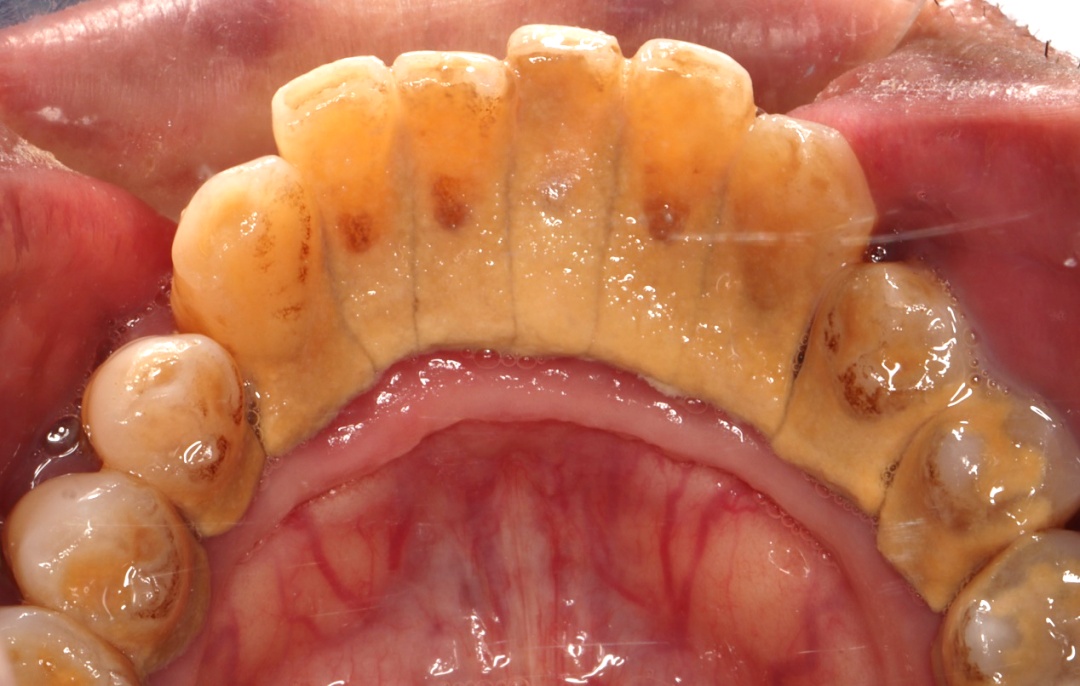

人老掉牙不是必然规律,老年人只要口内还有牙齿就应每天早晚刷牙,晚上睡前刷牙更重要。刷牙时不可大力横刷,以免损伤牙齿和牙龈。老年人需根据牙缝大小选用邻面清洁工具,牙龈萎缩不明显者可选用牙线。牙龈萎缩、有明显牙缝者,可选用牙间隙刷,并根据牙缝大小选择不同型号,使用时不要勉强进入,以免损伤牙龈。

预防根面龋可采取局部用氟方法,如使用含氟牙膏刷牙,定期到医院接受牙齿涂氟等。合理膳食也很重要,控制甜食摄入总量和频率,多吃新鲜蔬菜与水果。另外需要提醒的是,出现根面龋应及时治疗。